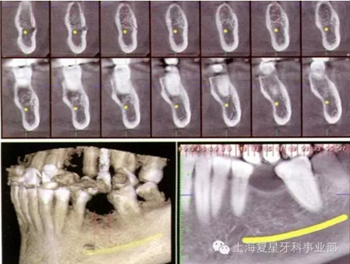

圖3a:左側(cè)下頜骨區(qū)CBCT掃描

一位55歲的健康女性,要求進行下頜磨牙的修復(fù)。她的主訴是:左側(cè)下頜第一磨牙(36#牙)由于幾年前根管治療失敗而拔除導(dǎo)致磨牙缺失。經(jīng)過包括臨床和圖片分析的完整診斷評估后,使用ProMax(普蘭梅卡;圖1和3a)三維掃面儀對左邊的下頜骨進行了CBCT掃描。

通過對牙冠的最后評估,考慮到重要的解剖結(jié)構(gòu),如下齒槽神經(jīng)和血管,設(shè)計種植體數(shù)字化的通過對牙冠的最后評估,考慮到重要的解剖結(jié)構(gòu),如下齒槽神經(jīng)和血管,設(shè)計種植體數(shù)字化的三維位置,獲得最便捷的修復(fù)和外科手術(shù)結(jié)果。然后將該虛擬設(shè)計的牙冠用于放射線模板(圖5)。

圖5:種植體的數(shù)字化三維位置的多面觀。注意如何用設(shè)計的虛擬冠作為數(shù)字化射線模板